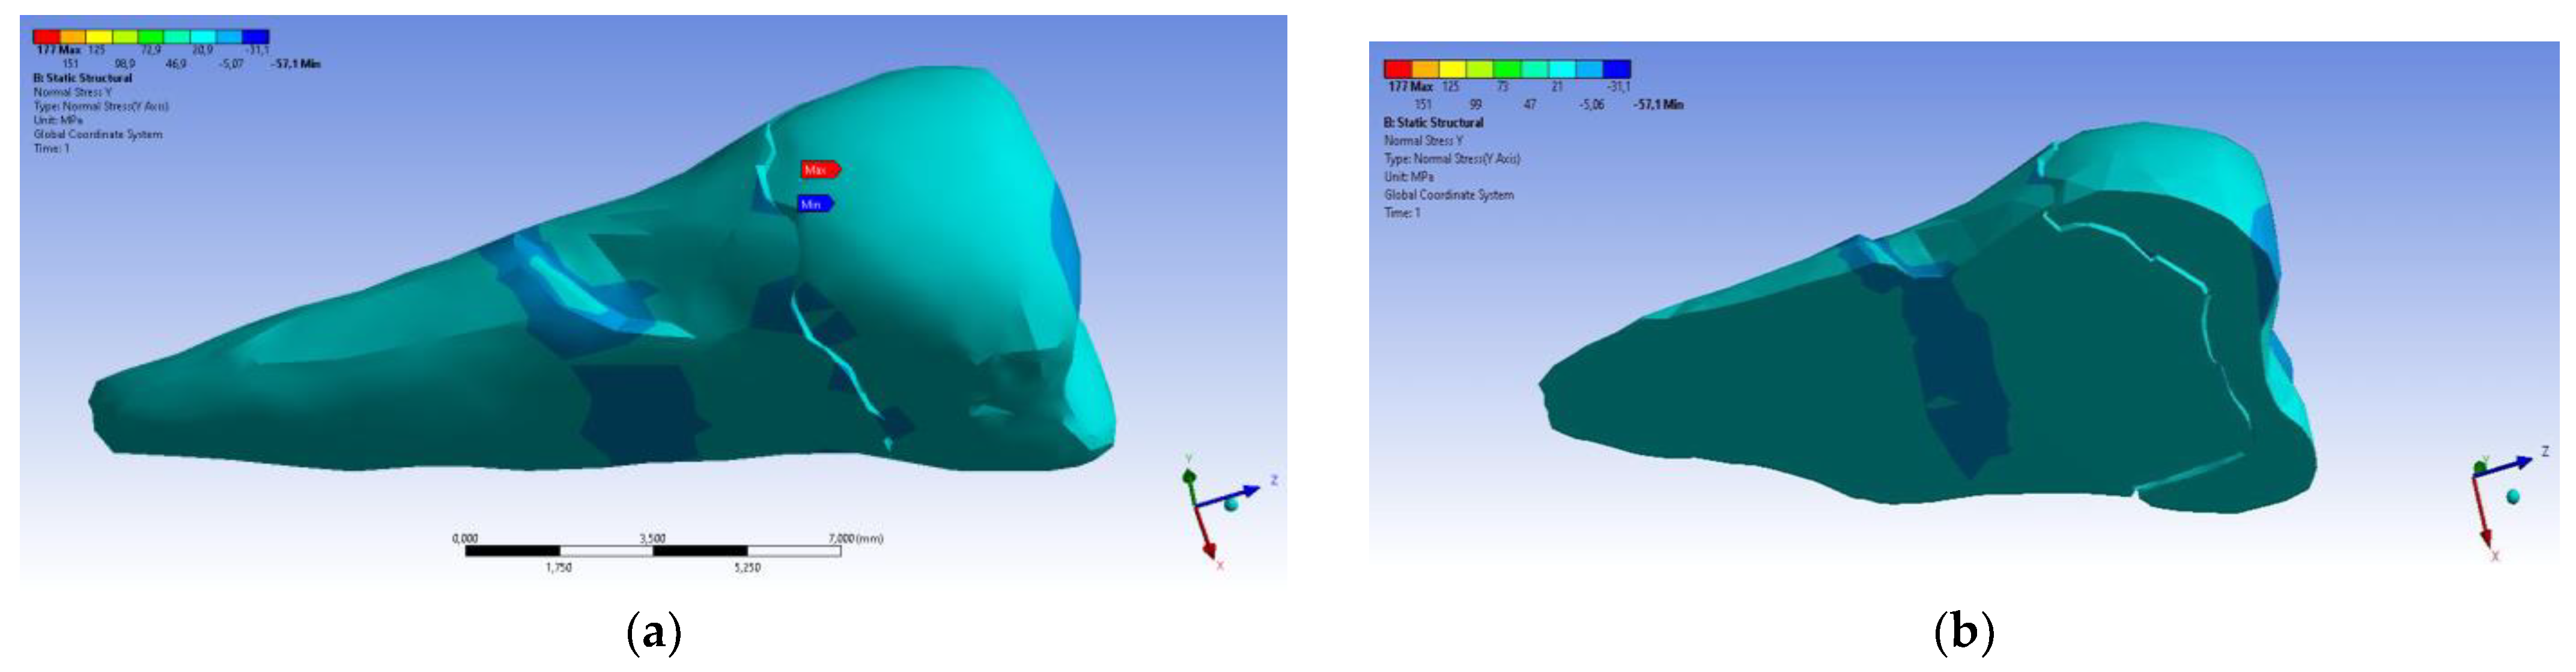

3. Finite Element Analysis (FEA) of Mandibular Right Premolars

| Total Deformation | Deformation in X Direction | Deformation in Y Direction | Deformation in Z Direction | Equivalent Stress | Normal Stress X | Normal Stress Y | Normal Stress Z | Maximum Main Stress | Minimum Main Stress | Tangential Stress XY | Tangential Stress YZ | Tangential Stress XZ | |

|---|---|---|---|---|---|---|---|---|---|---|---|---|---|

| Minimum | 0 mm | −4.24 × 10−3 mm | −2.52 × 10−2 mm | −1.56 × 10−2 mm | 1.01 × 10−6 MPa | −35.6 MPa | −57.1 MPa | −104 MPa | −15.2 MPa | −152 MPa | −43.7 MPa | −39.6 MPa | −56.3 MPa |

| Maximum | 2.77 × 10−2 mm | 3.57 × 10−3 mm | 6.98 × 10−4 mm | 4.78 × 10−3 mm | 248 MPa | 61.5 MPa | 177 MPa | 72.2 MPa | 195 MPa | 21.4 MPa | 44.2 MPa | 117 MPa | 22.2 MPa |

| Minim. in | Cementum | Cementum | Enamel | Enamel | Cementum | Cementum | Enamel | Enamel | Enamel | Cementum | Enamel | Enamel | Cementum |

| Maxim. in | Enamel | Enamel | Cementum | Enamel | Cementum | Enamel | Enamel | Enamel | Enamel | Enamel | Cementum | Cementum | Cementum |